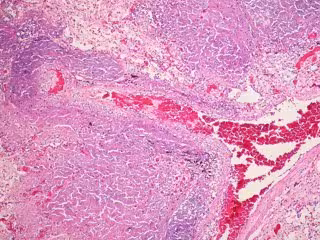

Tuberculosis

FLICKER/ PULMONARY PATHOLOGY

La tuberculosis afecta normalmente a los pulmones, si bien la bacteria la origina suele desarrollarse tan solo en las personas que tienen un sistema inmunológico debilitado.